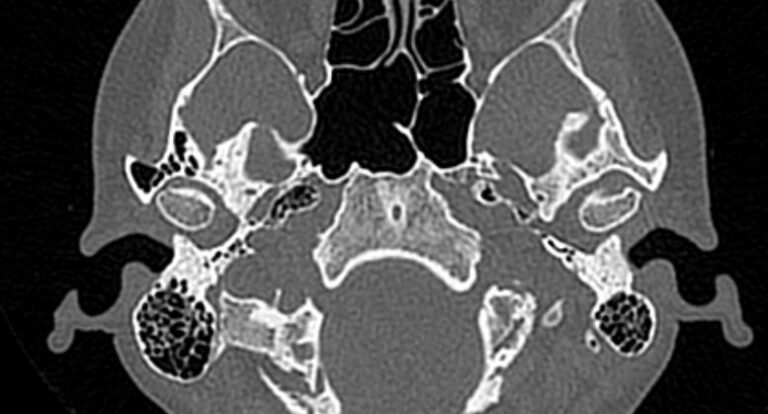

Наиболее точным и информативным методом диагностики костной патологии ВНЧС является мультиспиральная компьютерная томография. КТ относится к лучевым методам исследования, то есть для сканирования применяется рентгеновское излучение. В отличие от обычного рентгена томограф проводит одномоментно множество тончайших срезов исследуемой зоны, которые в дальнейшем проходят цифровую обработку. В результате получаются детальные снимки и трехмерные изображения области височно-нижнечелюстных суставов, которые позволяют проводить точную и достоверную диагностику.

В наших диагностических центрах установлены новейшие мультиспиральные компьютерные томографы экспертного уровня TOSHIBA AQUILION. Оснащение аппаратов позволяет получать послойные снимки и 3D-изображения области ВНЧС в мельчайших подробностях. При этом скоростное мультисрезовое сканирование обеспечивает минимальную дозу рентгеновского облучения для пациента.

Компьютерная томография позволяет оценить состояние костных структур височно-нижнечелюстных суставов, так как рентгеновские лучи хорошо задерживаются костной тканью. Для повышения диагностических возможностей компьютерной томографии в ряде случаев дополнительно проводится контрастное усиление путем внутривенного введения йодсодержащего контрастного препарата. Эта методика применяется для улучшения визуализации мягких тканей, которые хуже видны при нативном исследовании.

С помощью КТ можно оценить состояние костной ткани суставных головок нижней челюсти, внутрисуставного мениска, суставной капсулы, связочного аппарата и жевательных мышц.

При проведении мультиспиральной КТ можно выявить следующие патологии височно-нижнечелюстных суставов:

- Субкортикальные кисты (полость, образующаяся на месте суставной головки нижней челюсти в результате резорбции (то есть разрушения) костной ткани;

- Доброкачественные и злокачественные новообразования костных структур суставов или близлежащих мягких тканей.